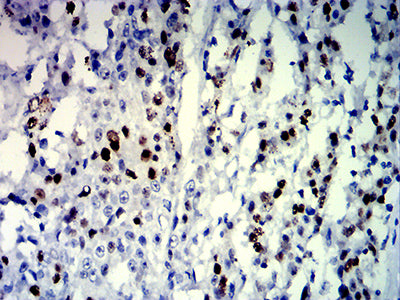

Immunohistochemical analysis of paraffin-embedded human lung cancer tissues using MKI67 mouse mAb with DAB staining.

Immunohistochemical analysis of paraffin-embedded human liver cancer tissues using MKI67 mouse mAb with DAB staining.

Immunohistochemical analysis of paraffin-embedded human esophageal cancer tissues using MKI67 mouse mAb with DAB staining.